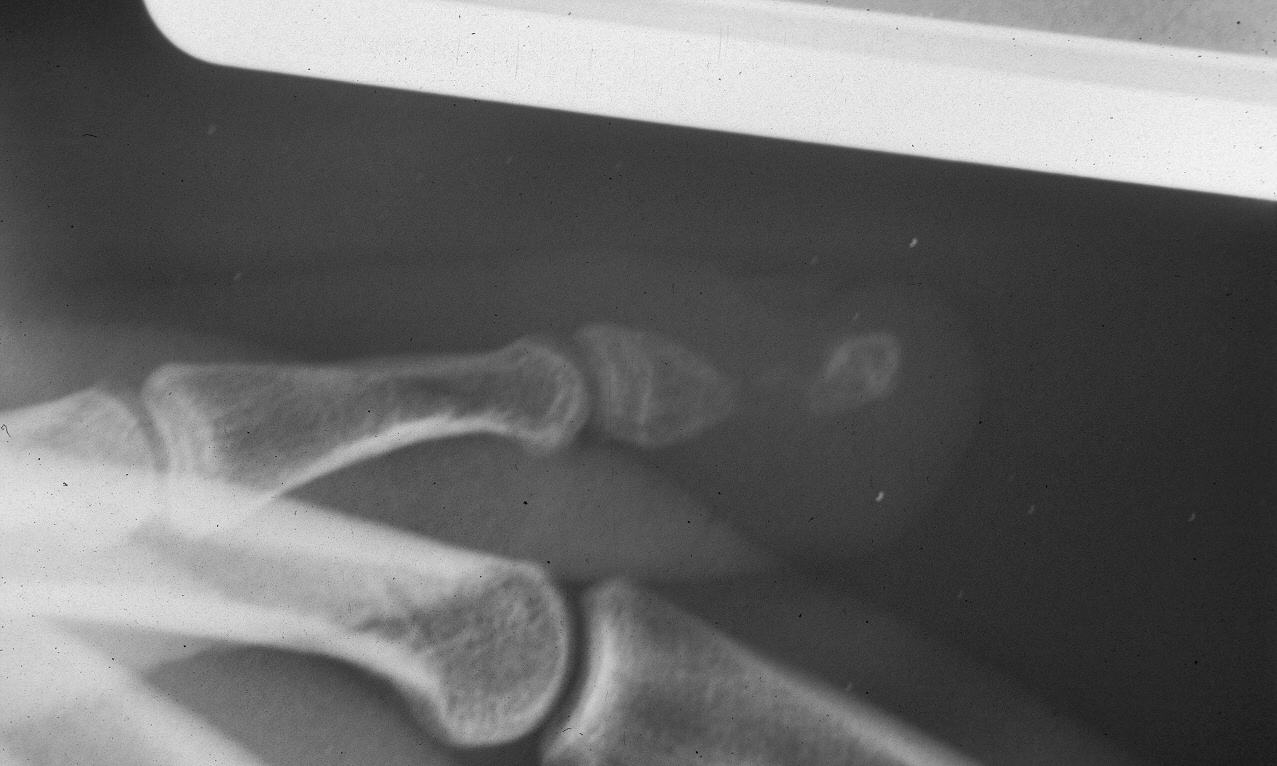

Case 1. This patient had an unstable small fingertip following a saw injury which resulted in loss of the central half of the distal phalanx of the small finger.

A palatal expansion clamp with a turnbuckle mechanism was used to design a progressively lengthening external fixator to restore length of the distal phalanx before reconstruction with a bone graft, here shown on a plastic sawbone model. This device is available at http://www.greatlakesortho.com and other orthodontic supplier retailers (no commercial interest).